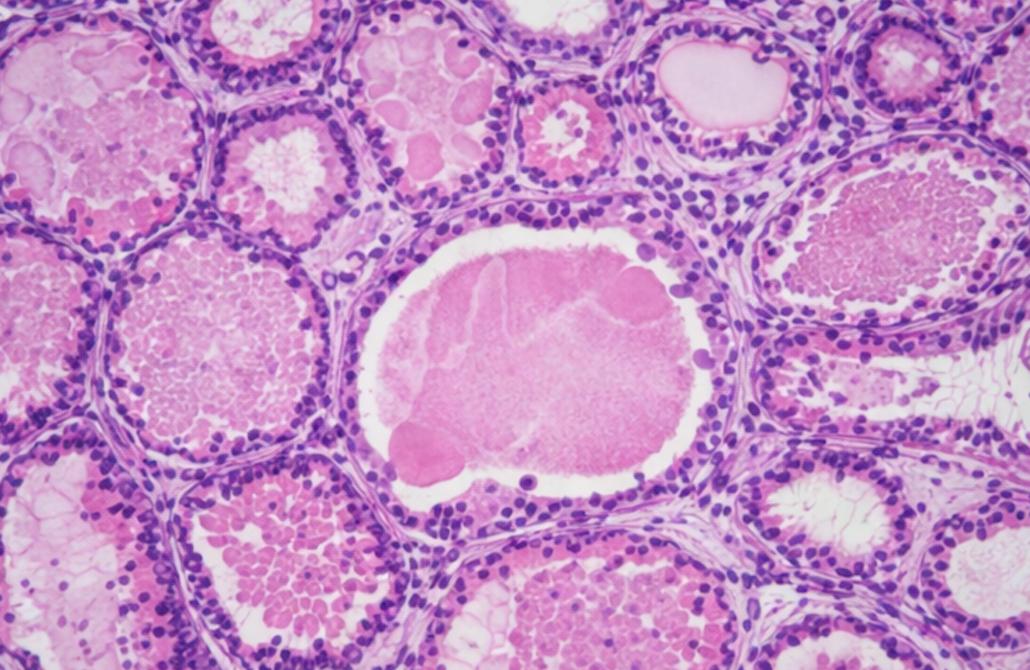

Histology

High-resolution digitization of tissue samples with advanced pattern recognition for pathological evaluation (beta)